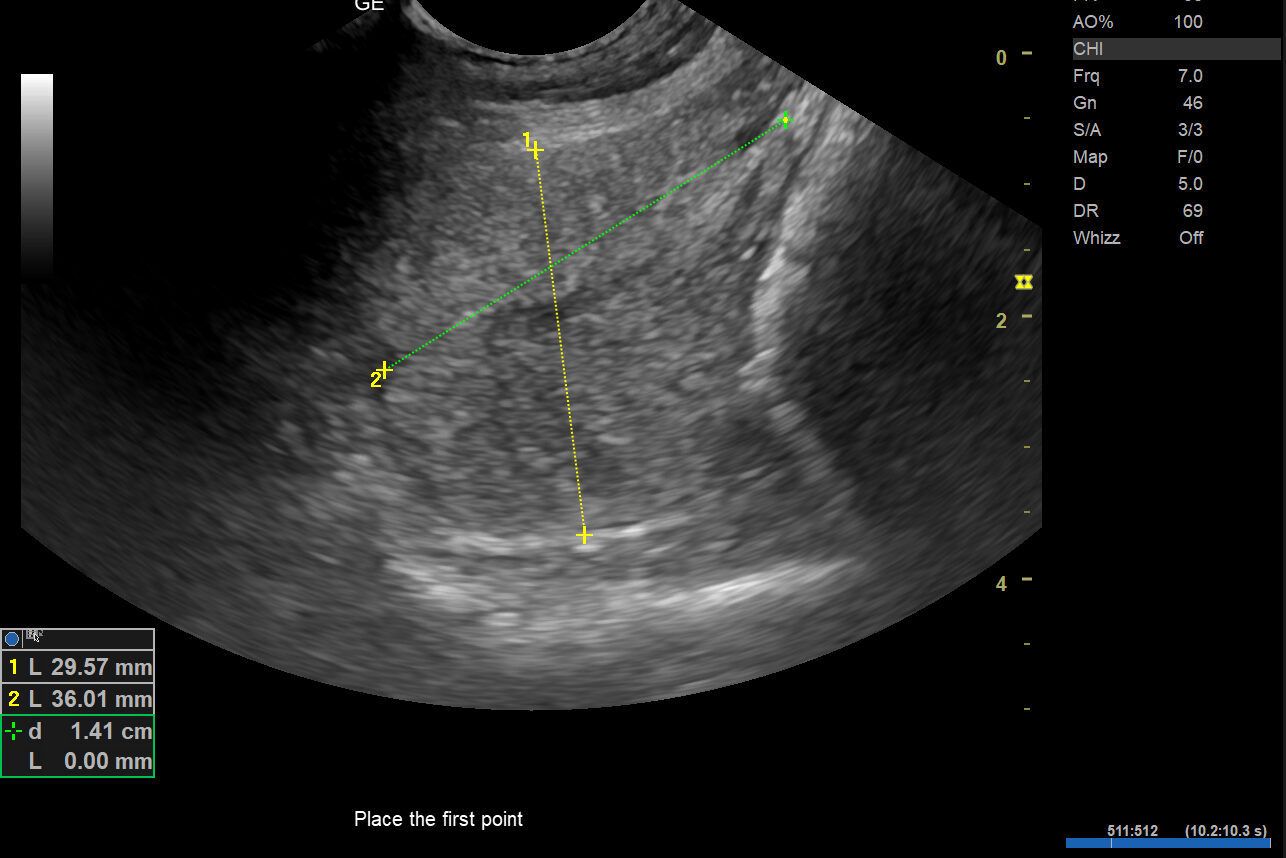

Under utredningen ble det oppdaget at Dino hadde en galleblære fylt med tykt slim, salter og grus. Tilstanden kalles galleblæremukocele. Dette er en alvorlig sykdom der innholdet i galleblæren blir unormalt tykt og hindrer normal tømming.

Ubehandlet kan galleblæren sprekke og føre til bukhinnebetennelse, som er livstruende. Diagnosen stilles ved ultralyd, hvor man ofte ser et karakteristisk mønster inne i galleblæren.